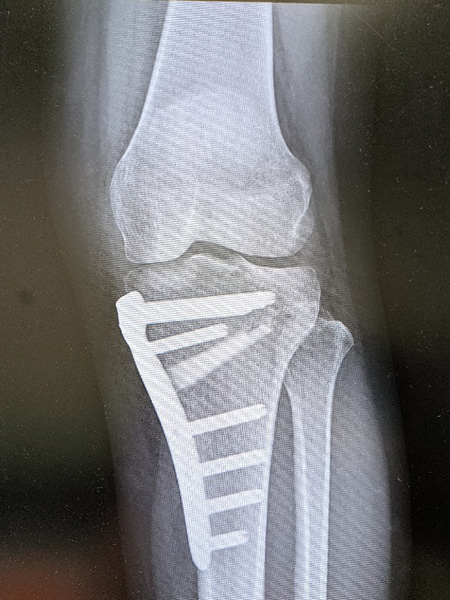

脛骨近位骨切り術

骨切り術は、膝の骨の角度を調整し、関節の負担を分散し痛みの軽減を図る手術です。通常関節鏡視下での半月板手術と併用されることが多く、自身の関節を温存できるため、スポーツや仕事で膝をよく使う方やどうしても人工関節に抵抗がある活動性の高い方に適しています。基本的に術後1年程度で抜釘します。

内側開大脛骨近位骨切り術軽度のO脚変形に対し行われます。

逆V脛骨近位骨切り術高度のO脚変形に対し行われます。